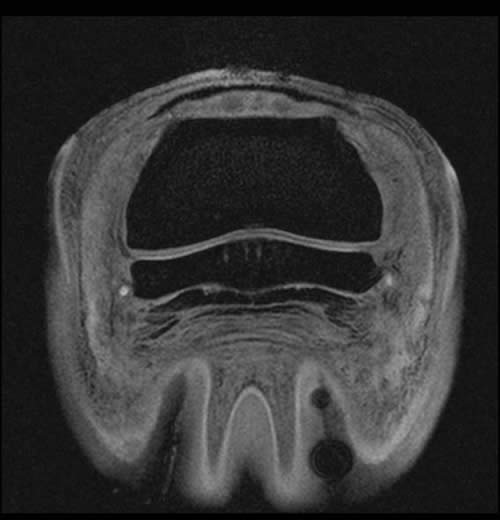

Figure 3: Tranverse 3D Flash MRI sequence with fat suppression of a horse’s foot; focal dorsal fibrillations of the DDFT can be appreciated (white arrows). Concurrent areas of fibrocartilage loss from the palmar surface of the navicular bone are certainly present but harder to recognize.